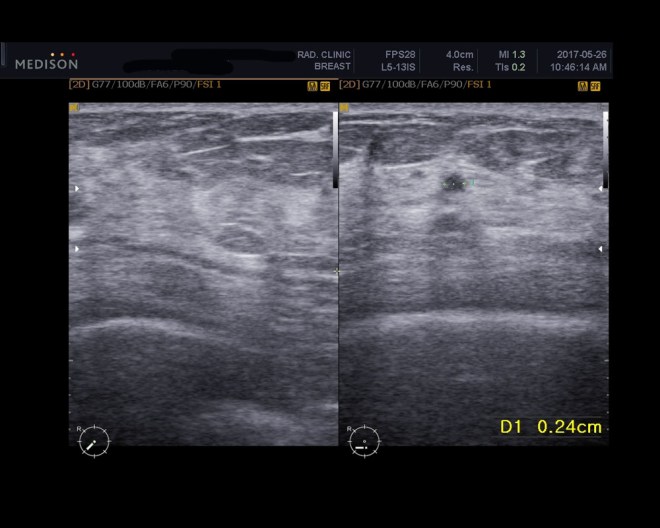

• 2017년 5월 26일 초음파상 종양완전소실  2.4mm의 양성으로 보이는 흔적남음

이 환자는 1년간 내 치료를 잘 따라 주었고 마음이 안정이 되어서 현재 사회생활도 하고 있다. 5월중에 초음파를 다시 비교하였다. 2017년 1월달에 추적검사를 하였고 다시금 5개월 뒤에 추적검사를 하였다.

2017년 5월 26일 초음파 추적검사

우지연 1-1.JPG

우지연 1-6.jpg

이미 판명된 우측 아래쪽 바깥 사면의 유방암으로 화학치료와 방사선을 받은 상태.

특별히 설명할 만한 잔여의 종양이나, 재발된 종양은 보이지 않는다. 조그마한 미세 석회화와 비정형의 낮은 조영증강의 부분이 보이는데 이는 아마도 방사선 치료 후의 변화로 보인다.

조그마한 정형을 가지지 않는 저밀도의 부분이 오른쪽 7시 방향에 여전히 보이는데 이는 이전 초음파 상에서 보였던 것과 변화가 없다. 아마도 양성의 부분으로 보인다.

양쪽 겨드랑이와 왼쪽 유방에는 특별한 것이 없다. 6개월 뒤에 다시 추적할 것을 권유한다.